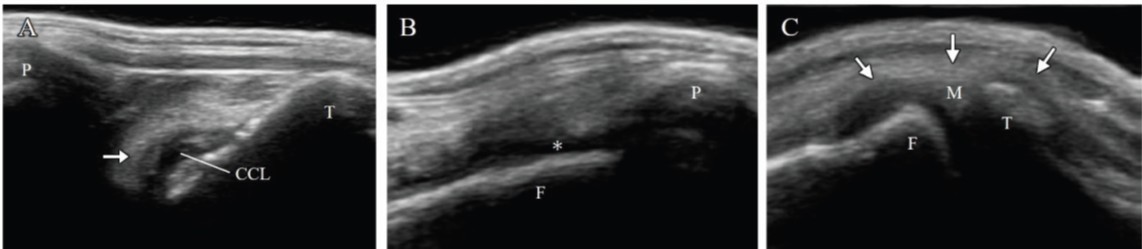

膝关节超声显示右膝关节完全CCLR,严重的关节积液和内侧支撑,但内侧半月板未受伤(图2A-C)。此外,左膝关节观察到部分CCLR和轻度关节积液。

图2. 首次就诊时右膝关节超声可以看到前交叉韧带完全断裂(箭头,A)和严重的关节积液(星号,B)。尽管可以看到内侧支撑(箭头,C),但内侧半月板的后角未见损伤(C)。CCL,前交叉韧带;F,股骨;M,内侧半月板;P,髌骨;T,胫骨。